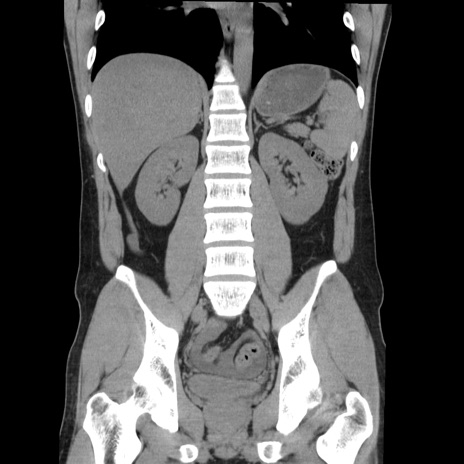

症例36(冠状断像)

【症例】20歳代 男性

【主訴】心窩部痛

【現病歴】今朝より上腹部痛あり。一旦軽快していたが再度出現したため救急要請。昨日夕に白身の魚を含む刺身を食べた。

【身体所見】BP 136/89mmHg、HR 74/min、BT 37.0℃、腹部:膨満、軟、心窩部に圧痛あり。反跳痛なし、筋性防御なし、腸雑音やや亢進あり。

【データ】WBC 17700、CRP 0.48